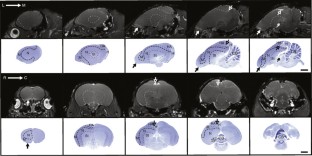

Many of the 5,500 threatened species of vertebrates found worldwide are highly protected and generally unavailable for scientific investigation. Here we describe a noninvasive protocol to visualize the structure and size of brain in postmortem specimens. We demonstrate its utility by examining four endangered species of kiwi (Apteryx spp.). Frozen specimens are thawed and imaged using MRI, revealing internal details of brain structure. External brain morphology and an estimate of brain volume can be reliably obtained by creating 3D models. This method has facilitated a comparison of brain structure in the different kiwi species, one of which is on the brink of extinction. This new approach has the potential to extend our knowledge of brain structure to species that have until now been outside the reach of anatomical investigation.

Corfield, J., Wild, J., Cowan, B. et al. MRI of postmortem specimens of endangered species for comparative brain anatomy. Nat Protoc 3, 597–605 (2008). https://doi.org/10.1038/nprot.2008.17